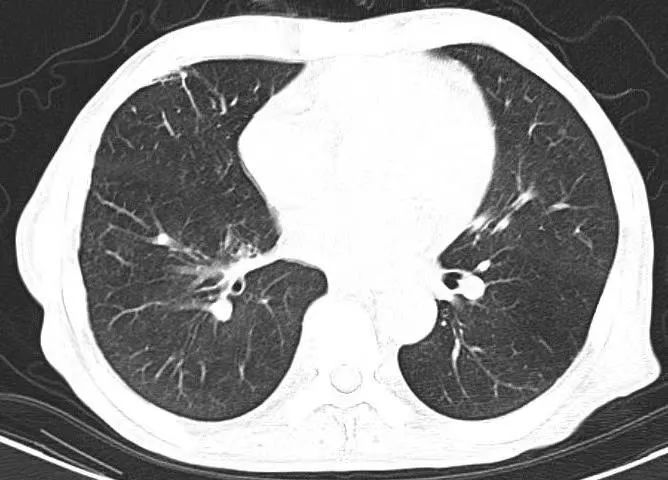

(第三次胸部CT)

在重症医学科团队的科学救治和精心照料下,患者情况一天比一天好转,病情逐渐稳定。抗感染、抗心衰10天后,复查胸部CT,提示:感染灶基本消散、胸膜腔积液完全吸收、右下肺局限性肺不张复张,双肺从白乎乎变得清清亮亮。B型钠尿肽也从3390.00pg/ml降至121.30pg/ml。大家都松了一口气,悬着的一颗心终于可以稍稍放下。十多天后,经过全面评估,患者达到出院标准。